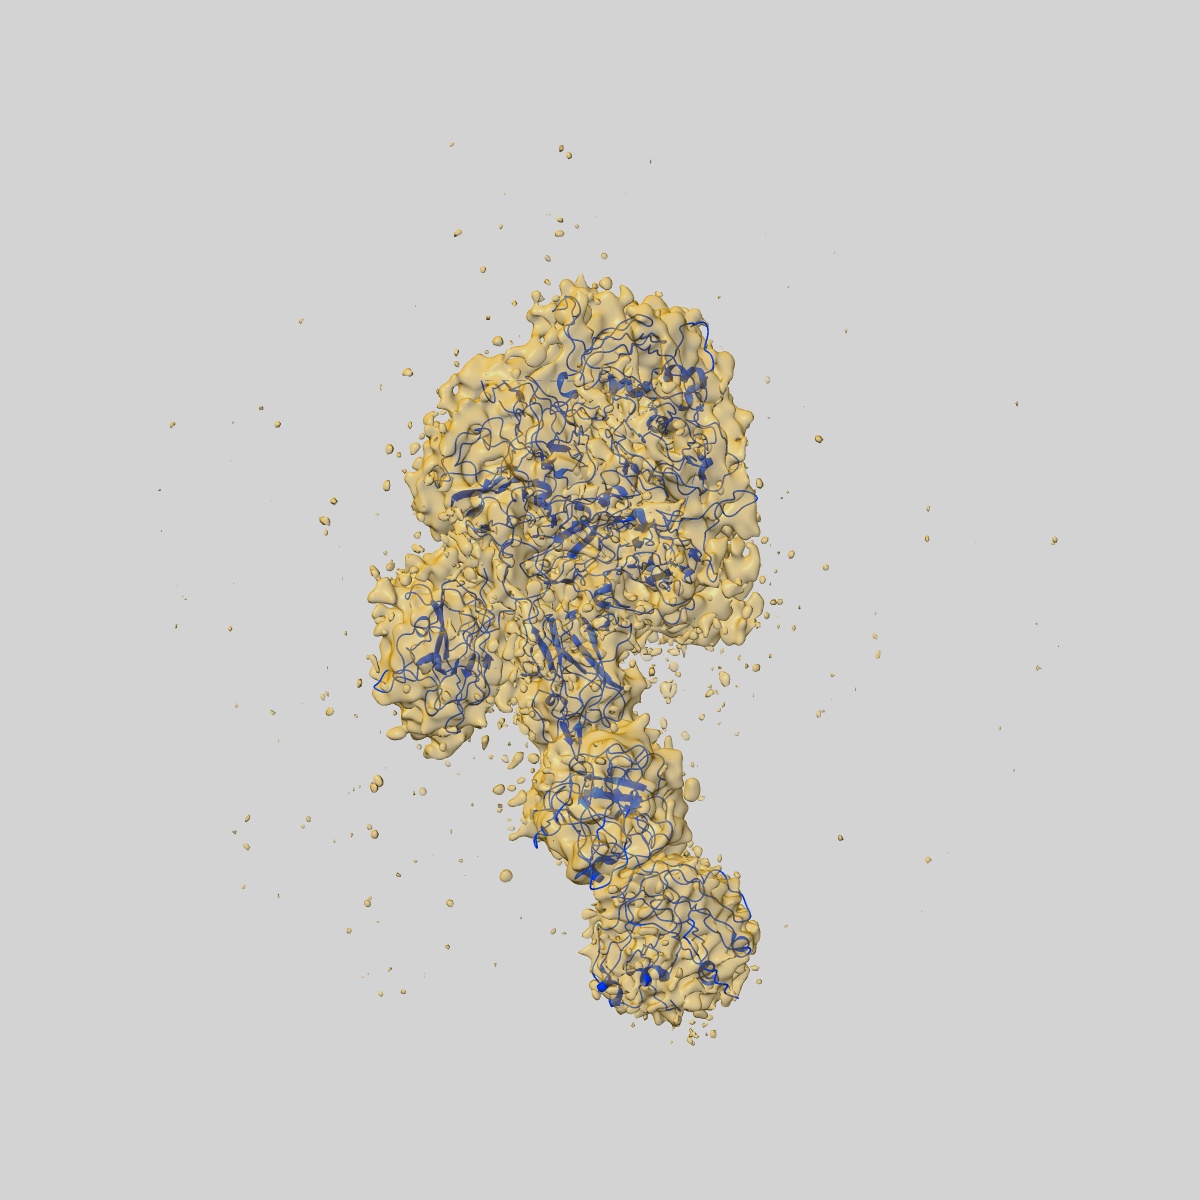

Coagulation factor VIII bound to a patient-derived anti-C1 domain antibody inhibitor

Sample: Structure of coagulation factor VIII bound to a patient-derived anti-C1 domain antibody inhibitor

Structure of coagulation factor VIII bound to a patient-derived anti-C1 domain antibody inhibitor.